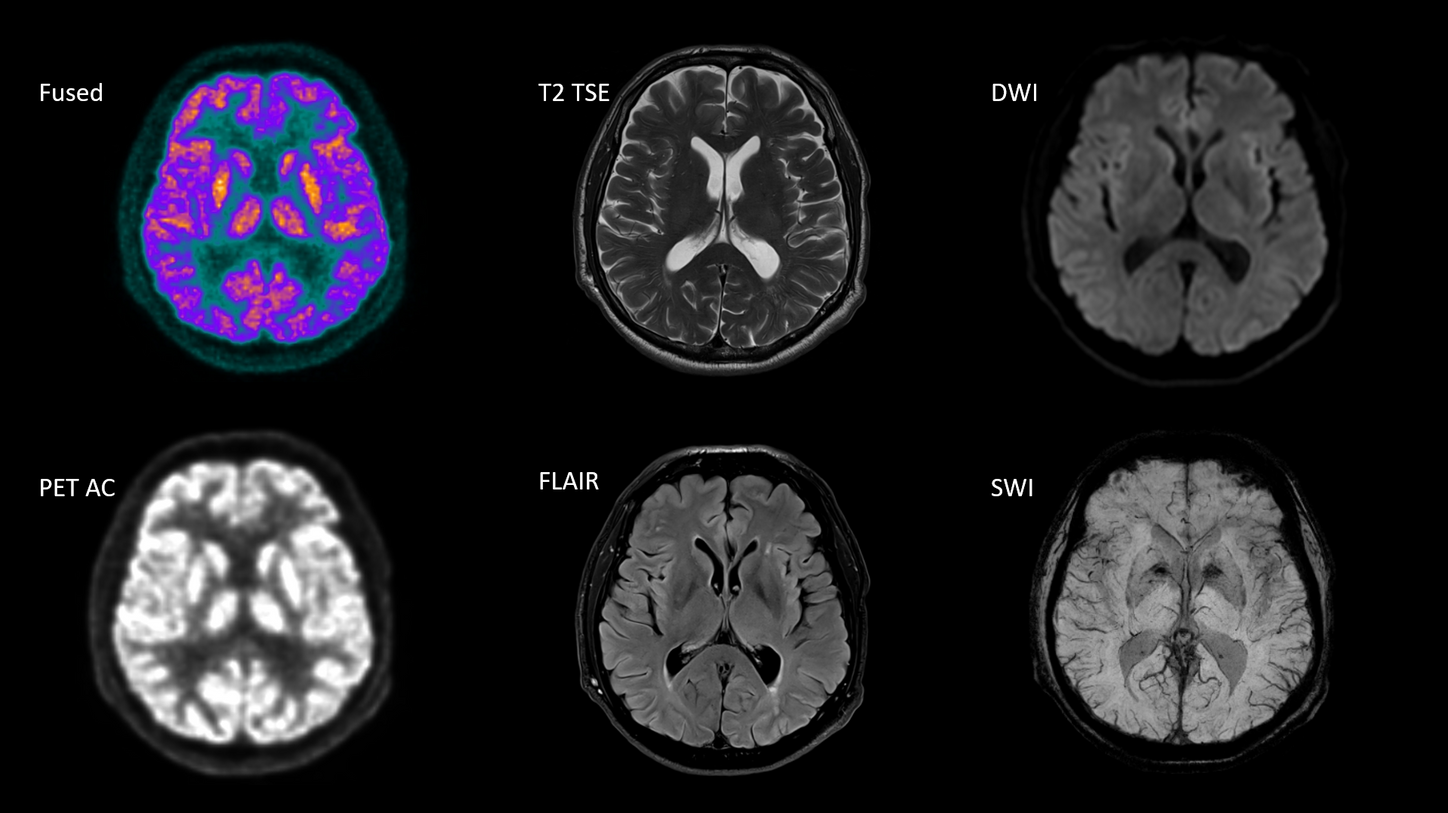

BIOGRAPH One is designed to excel in PET/MR precision to support confident diagnostic decisions. Featuring the Optiso UDR Pro detector with the largest 35 cm axial FOV2 in PET/MR, it is designed to enable comprehensive capture with excellent sensitivity and ultra-fast TOF3 in real time – delivering clear, detailed images.

Planned with Deep Resolve for accelerated acquisition and improved resolution in 2D and 3D applications4, BIOGRAPH One has the potential to make PET/MR exams faster than ever before. Designed with a powerful 3T magnet at its heart, BIOGRAPH One will deliver unparalleled performance with outstanding homogeneity, a large 55 x 55 x 50 cm³ field of view and robust gradient power.